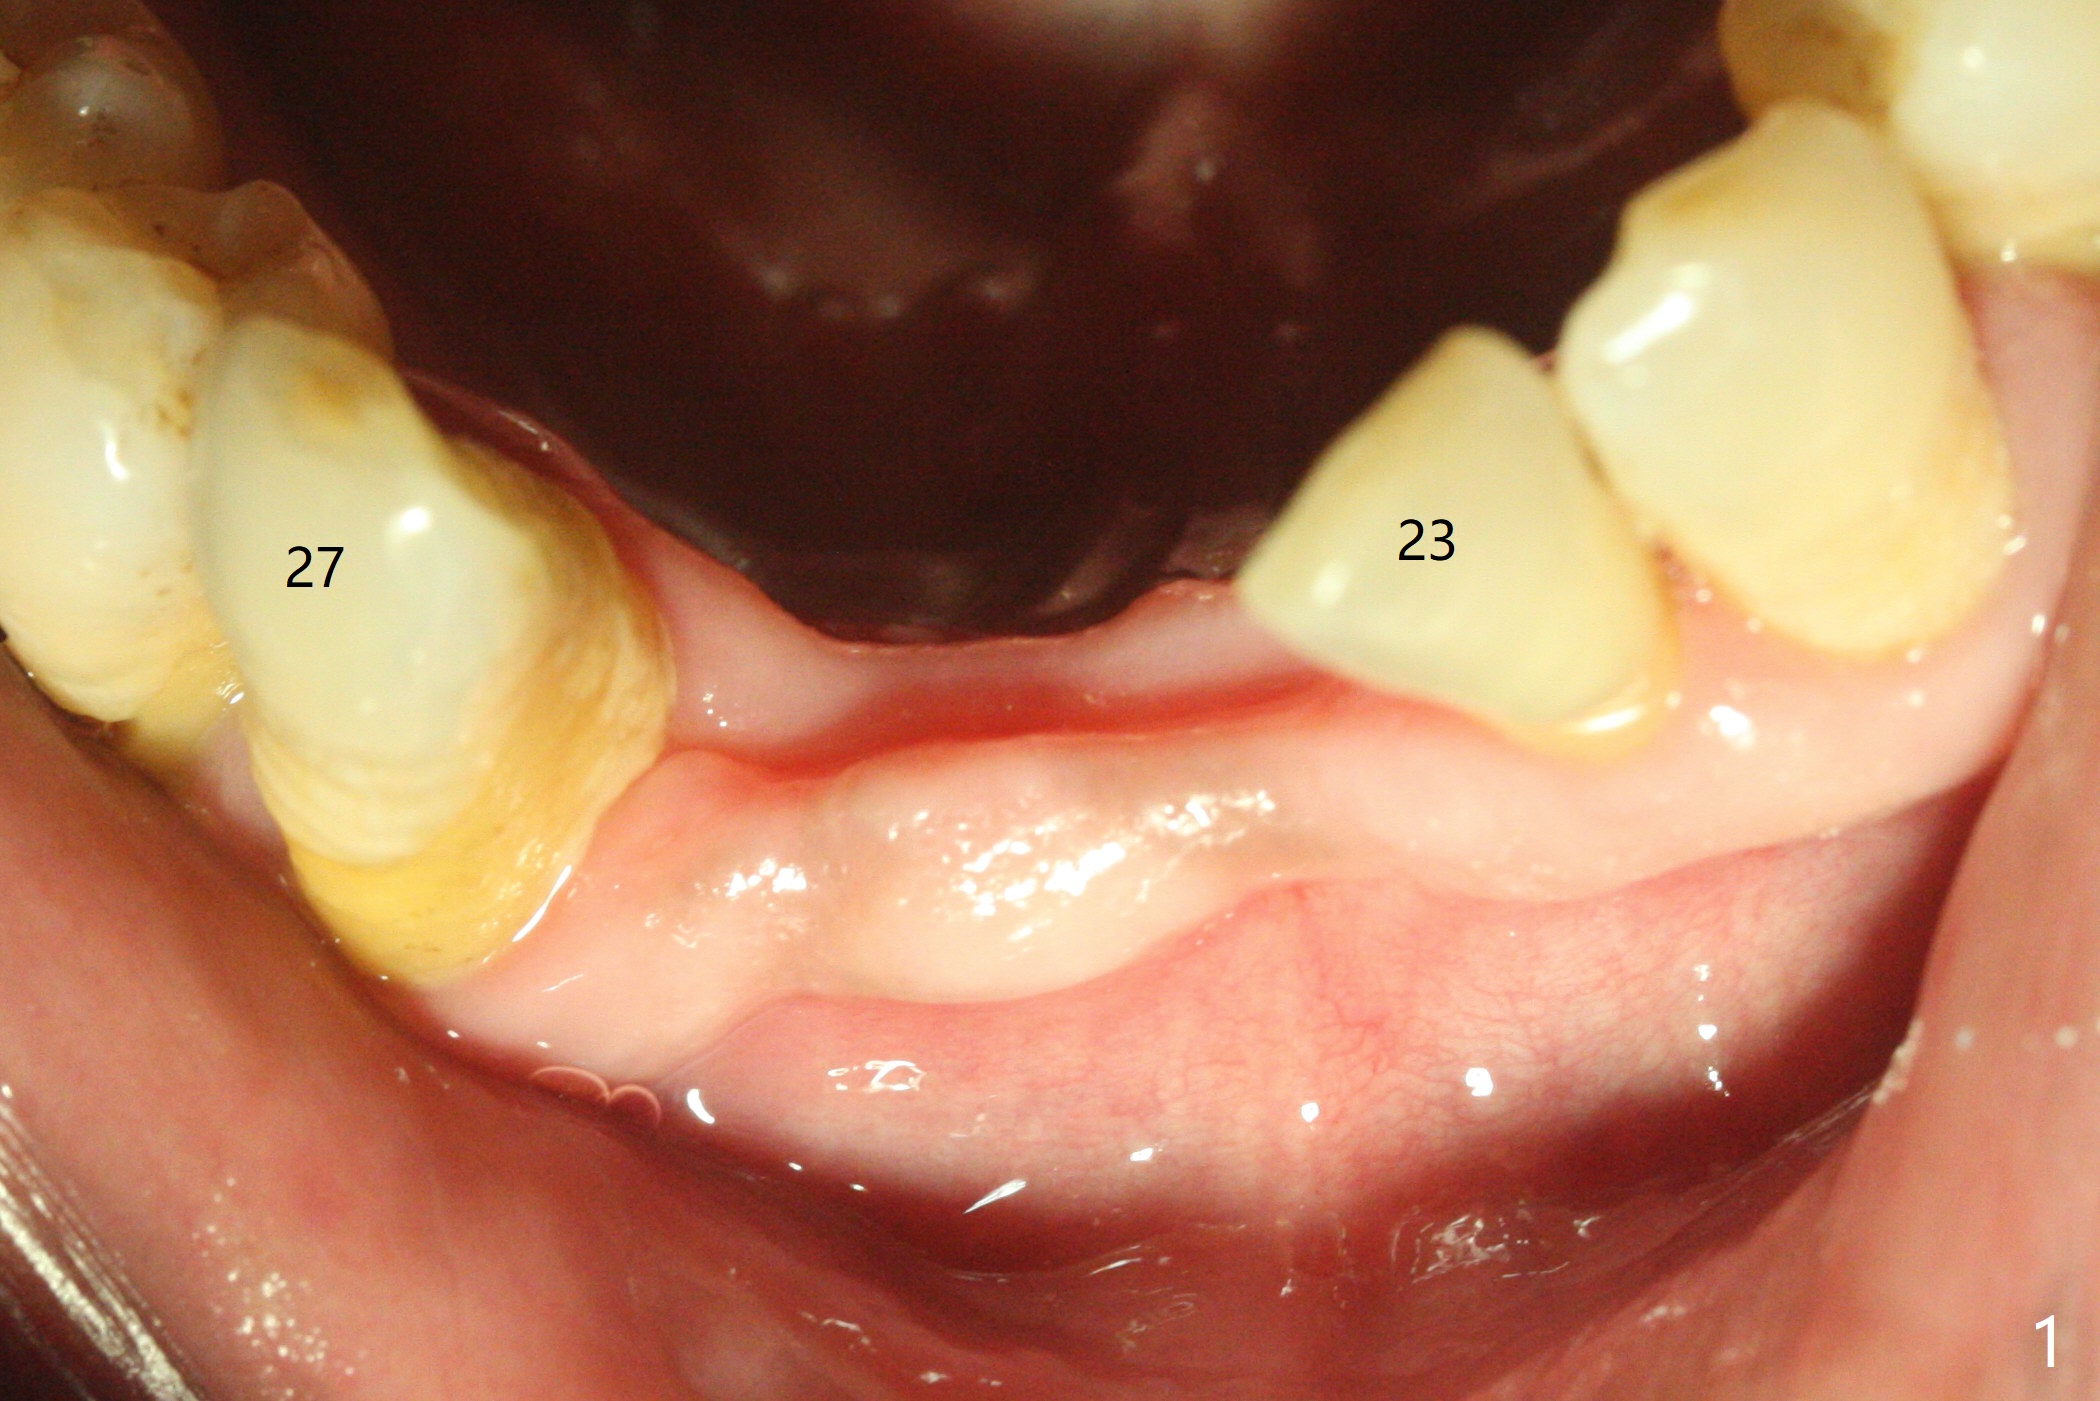

After placement of implant at #30 with high torque, osteotomy is prepared with 2.2 mm drill at #24 (M) first (Fig.1 before flap surgery). A 2.5 mm mini implant is placed < 10 Ncm (Fig.2,3). Since the ridge at #26 is apparently wider than that of #24 (Fig.1), a 3x11.5 mm implant is placed after the same drill (2.2 mm); insertion torque is ~ 35 Ncm. Bone graft is placed around the implants (Fig.2,3 *) before placement of PRF membrane. The patient is unpleased with our being unable to fabricate an immediate provisional (because of low torque at #24) as we have promised to. He is going to attend a wedding in fortnight. Instead periodontal dressing is applied. The latter is slight loose 1 week postop (Fig.4). There is apparently no bone loss 4 months postop with ~ 3 month provisional (Fig.5). The gingiva is healthy in spite of poor oral hygiene.